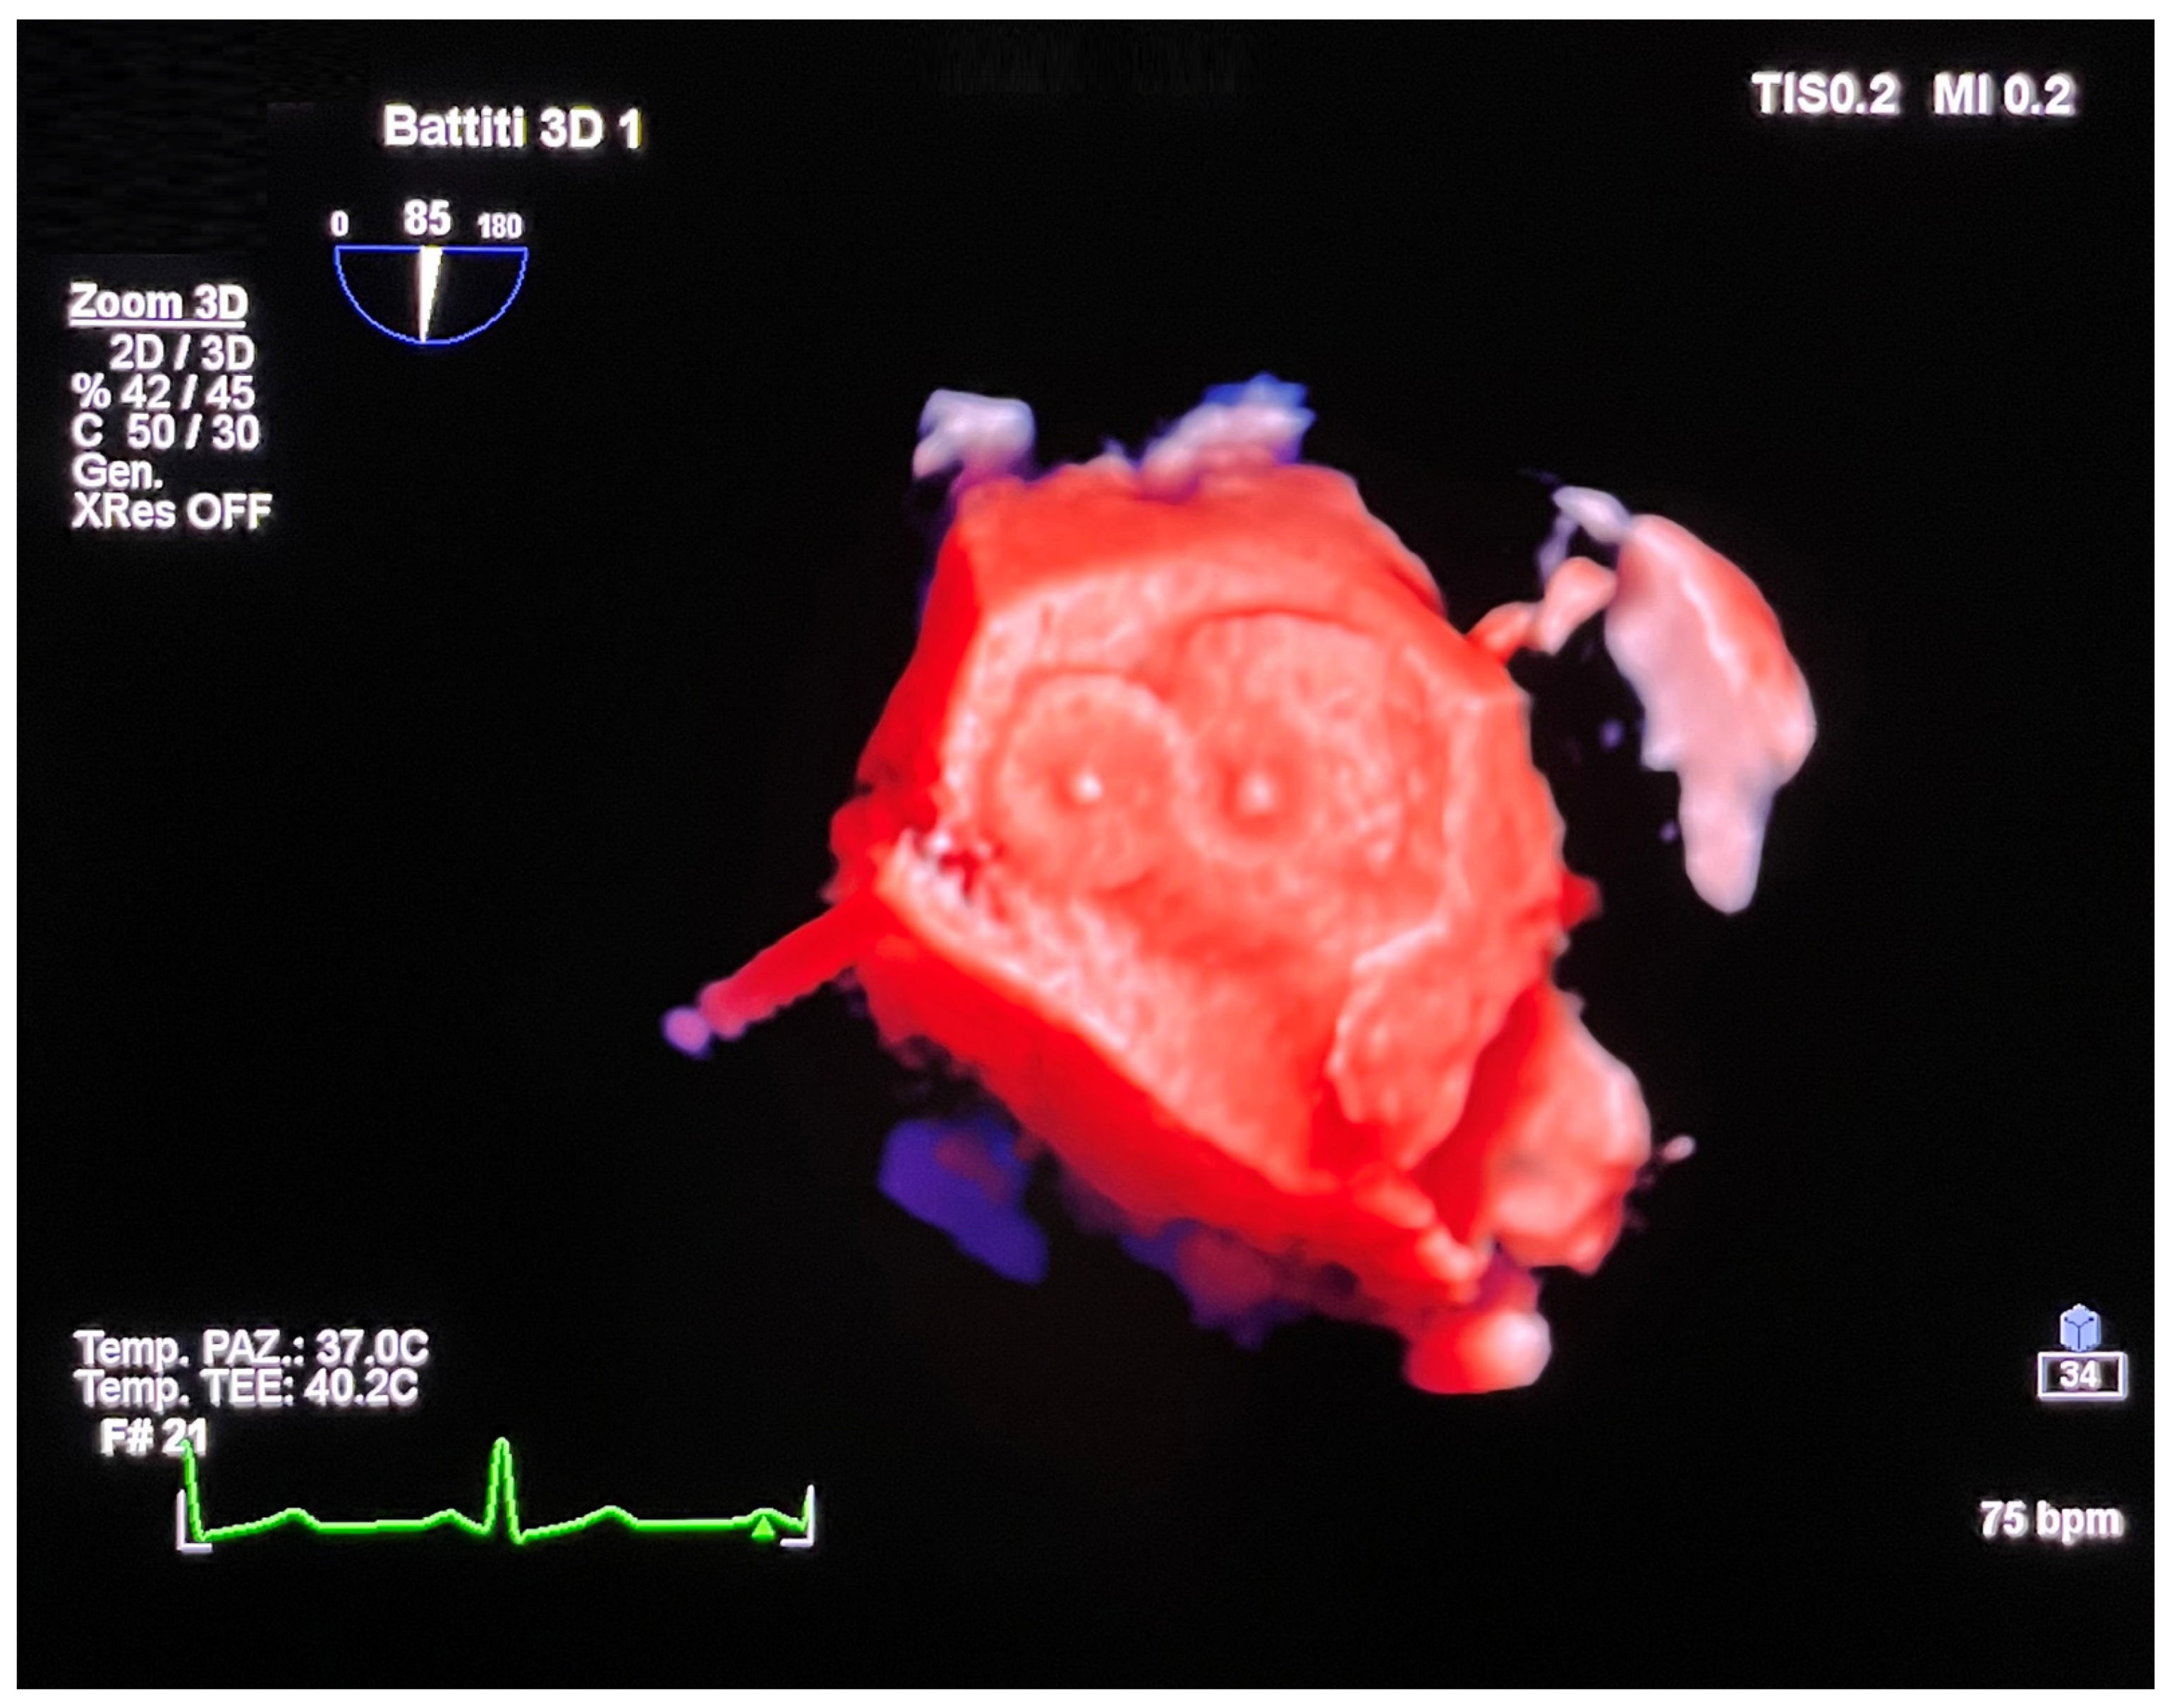

4. Leak Closure of Atrial Switch Operation Baffles

5. Fontan Conduit Fenestration Management